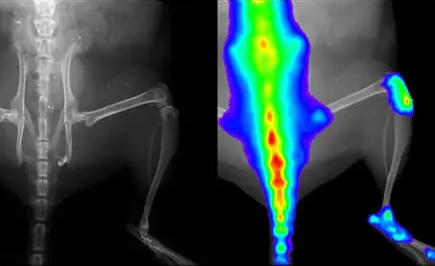

Metastaza nowotworu, znakowanie bioluminescencyjne: IVIS Spectrum CT